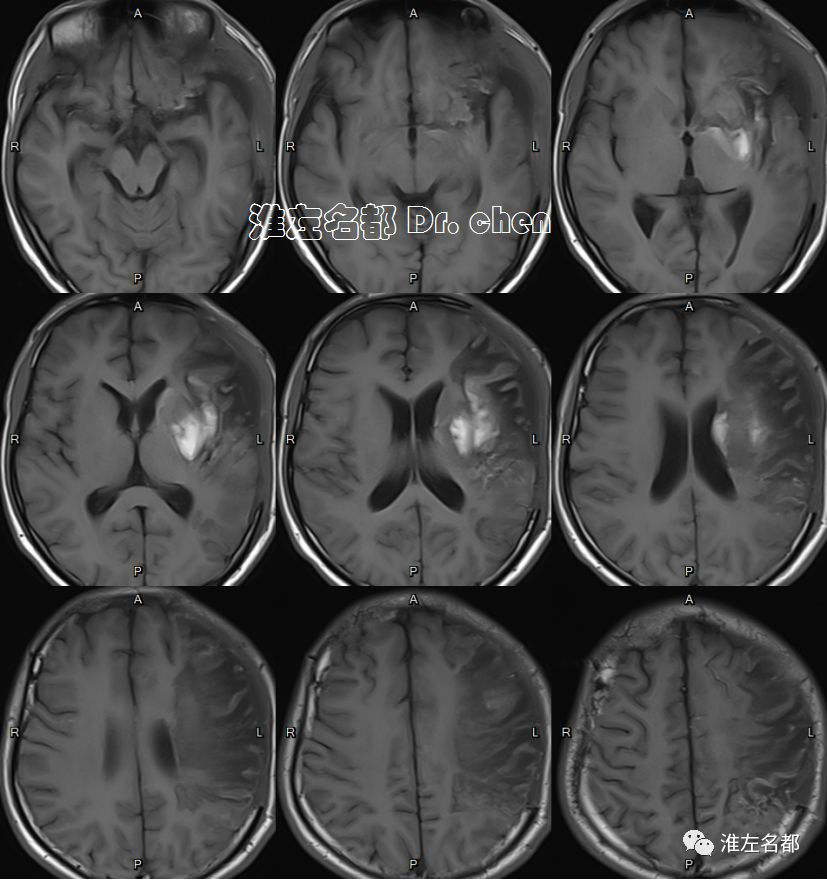

△T2WI、T1WI、FLAIR和SWI:左侧半球大面积亚急性梗死伴渗血,局部软化坏死。

△管壁高分辨MRI(增强T1-SPACE):左侧大脑中动脉主干管壁未见异常(橙箭),左侧颈内动脉远端管壁增厚和强化(红箭)。

△管壁高分辨MRI(增强T1-SPACE):左侧颈内动脉末端检测到夹层“内膜征”(橙箭)。